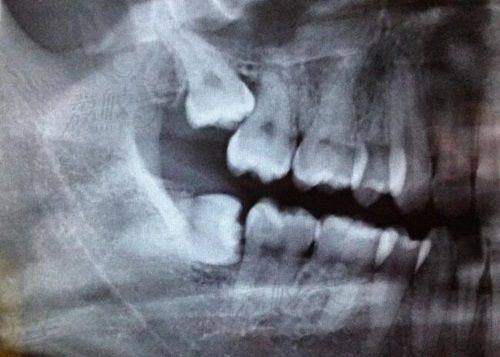

下巴后缩带牙套是否有用取决于导致下巴后缩的原因。

如果下巴后缩是由牙齿畸形导致的,戴牙套进行正畸治疗通常是有效的。不同类型的牙套对于下巴后缩有不同的矫正成效:

但对于因下颌骨发育问题导致的下巴后缩,可能需要结合其他治疗方法,如正颌手术等。在选择矫正方式时,患者应综合考虑个人的口腔状况、矫正目标、预算以及美观需求,并询问专精的正畸医师,以制定更合适的治疗计划。